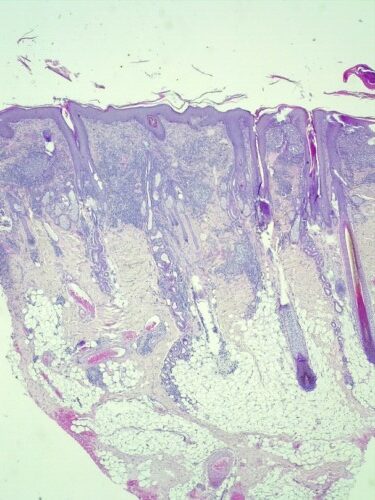

L’examen histopathologique de biopsies cutanées révèle une sévère dermatite granulomateuse lichénoïde et nodulaire périannexielle (photos 8 et 9). Les colorations PAS et fite faraco ne révèleront aucun agent pathogène.

Photo 8 : Examen histopathologique de biopsies cutanées (HES, x25) sévère dermatite nodulaire periannexielle